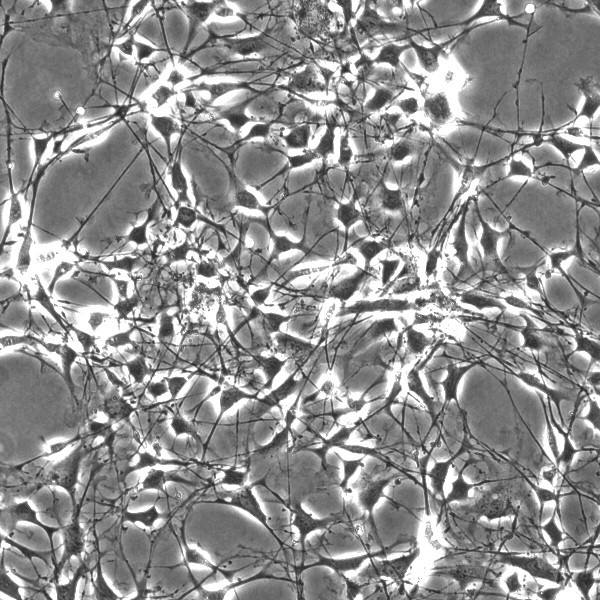

Schwann cells proliferation is required to ensure successful regeneration of damaged peripheral axons.

Schwann cells are essential for the maintenance of axonal homeostasis and the prevention of axonal degeneration via secretion of a variety of neurotrophins and also transfer essential molecules along the axons.

Graph showing the effect of basic Fibroblast growth factor (bFGF) and Doramapimod (p38 MAP kinase inhibitor) on the proliferation Schwann cells.

Co-cultures of primary Schwann cell and Sensory neurons